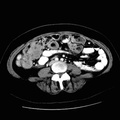

RADIOLOGY: FEMALE REPRODUCTIVE: Case# 33102: OVARIAN CA WITH METS (CALCIFIED). 53 year old female with a history of ovarian cancer from 1/96 with subsequent pelvic abscesses. She is on chemotherapy, but has not received radiation therapy. 1. Minimal change in multiple, scattered calcified masses in the abdomen and pelvis, although they are more prominent on todays scan. These probably represent recurrence of ovarian carcinoma. 2. Tiny loculated fluid collections in the pelvis. This was not definitely seen on earlier scan, and may represent abscess. 3. Left adrenal gland without change, probably representing adenoma.